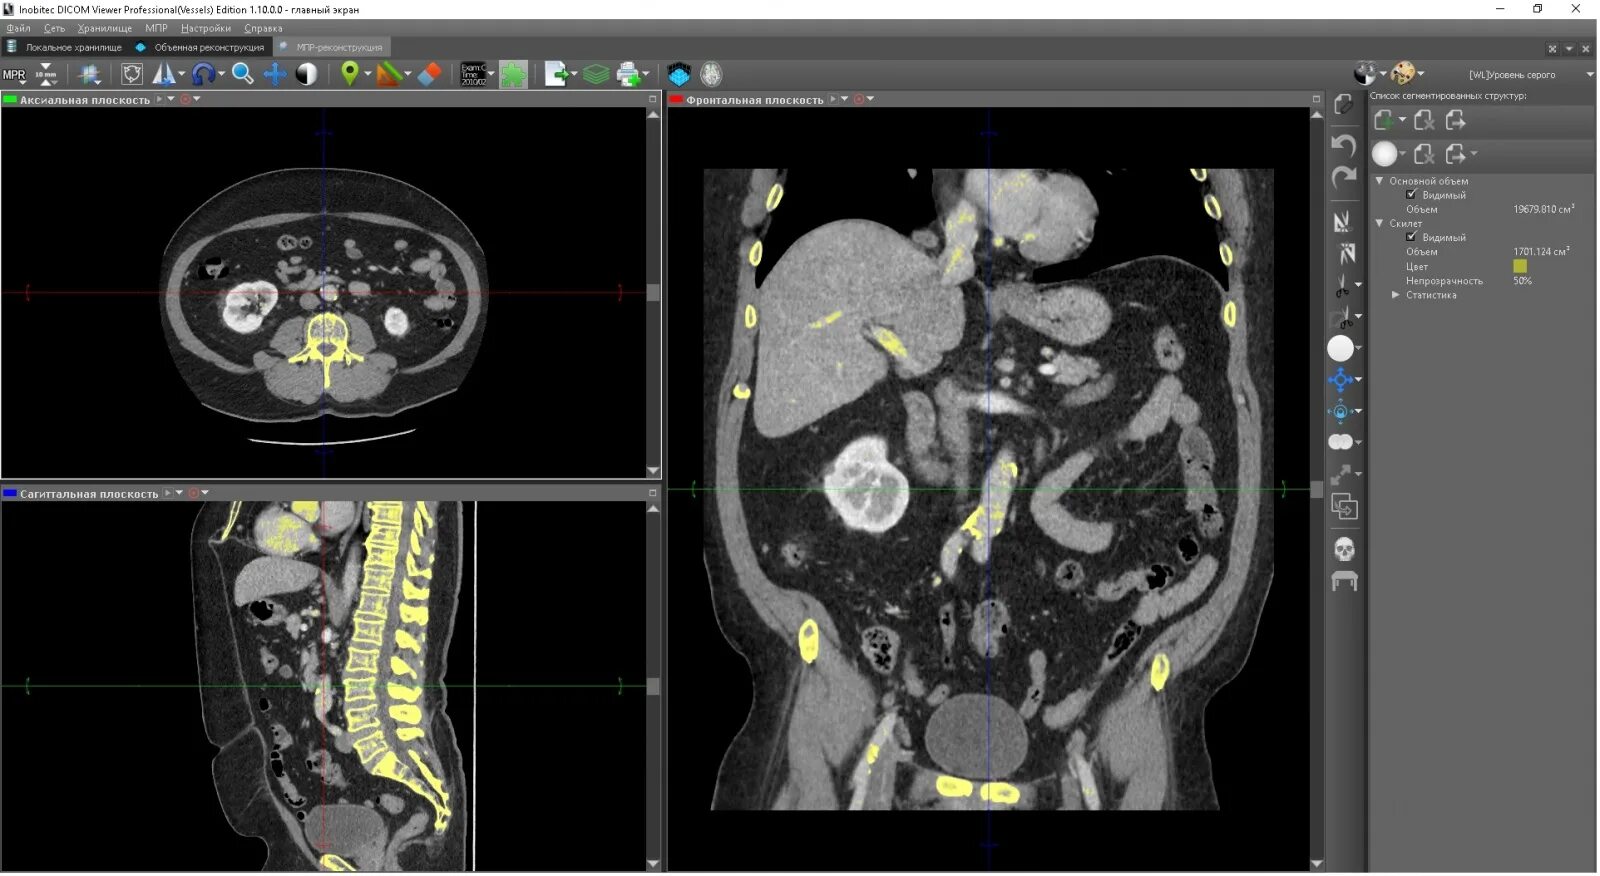

Dicomdir чем открыть снимки мрт